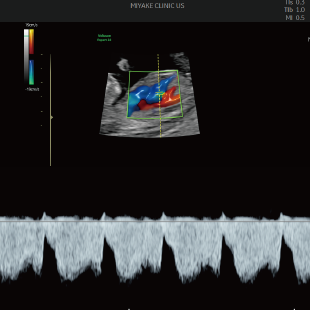

赤ちゃんの3~5%は、何らかの病気や医学的な介入を要する状態をもって生まれてくるといわれており、その中には、妊娠中・出生時・出生後に緊急の対応を要するものも含まれます。 特に先天性心疾患は比較的頻度が高く、約100人に1人の赤ちゃんが先天性心疾患を合併し、重症度や緊急性の高い症例(生後に入院や手術が必要な症例)は約1000人に4人といわれています。

Voluson Expert 22®(GEHealthcare)という産婦人科領域におけるハイエンド超音波診断装置を使用しています。 従来機種と比べ、より高精細な画像描出性能と高度な解析機能を備えており、 胎児の発育や形態をより詳細に観察することが可能です。